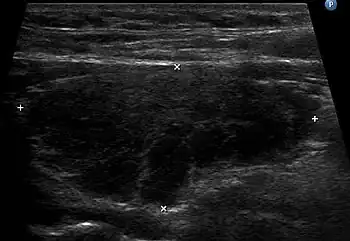

Ultrasound imaging of the thyroid gland (right lobe longitudinal) in a person with Hashimoto thyroiditis.